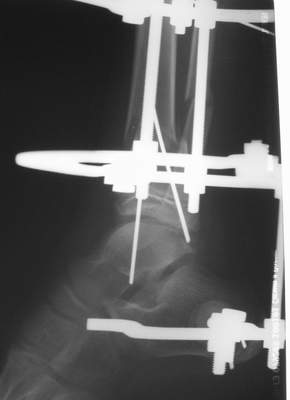

Вытяжение

|

Нашел в комп-ре схожий случай:

1) з/репозиция, 2) фиксация 2 спицами, 3) аппарат, 4) фиксационные

спицы удалены...

См. аттачт.

А можно было наложить аппарат и по поводу ложного сустава...

По крайней мере не было бы укорочения (пусть и в 2 см)...